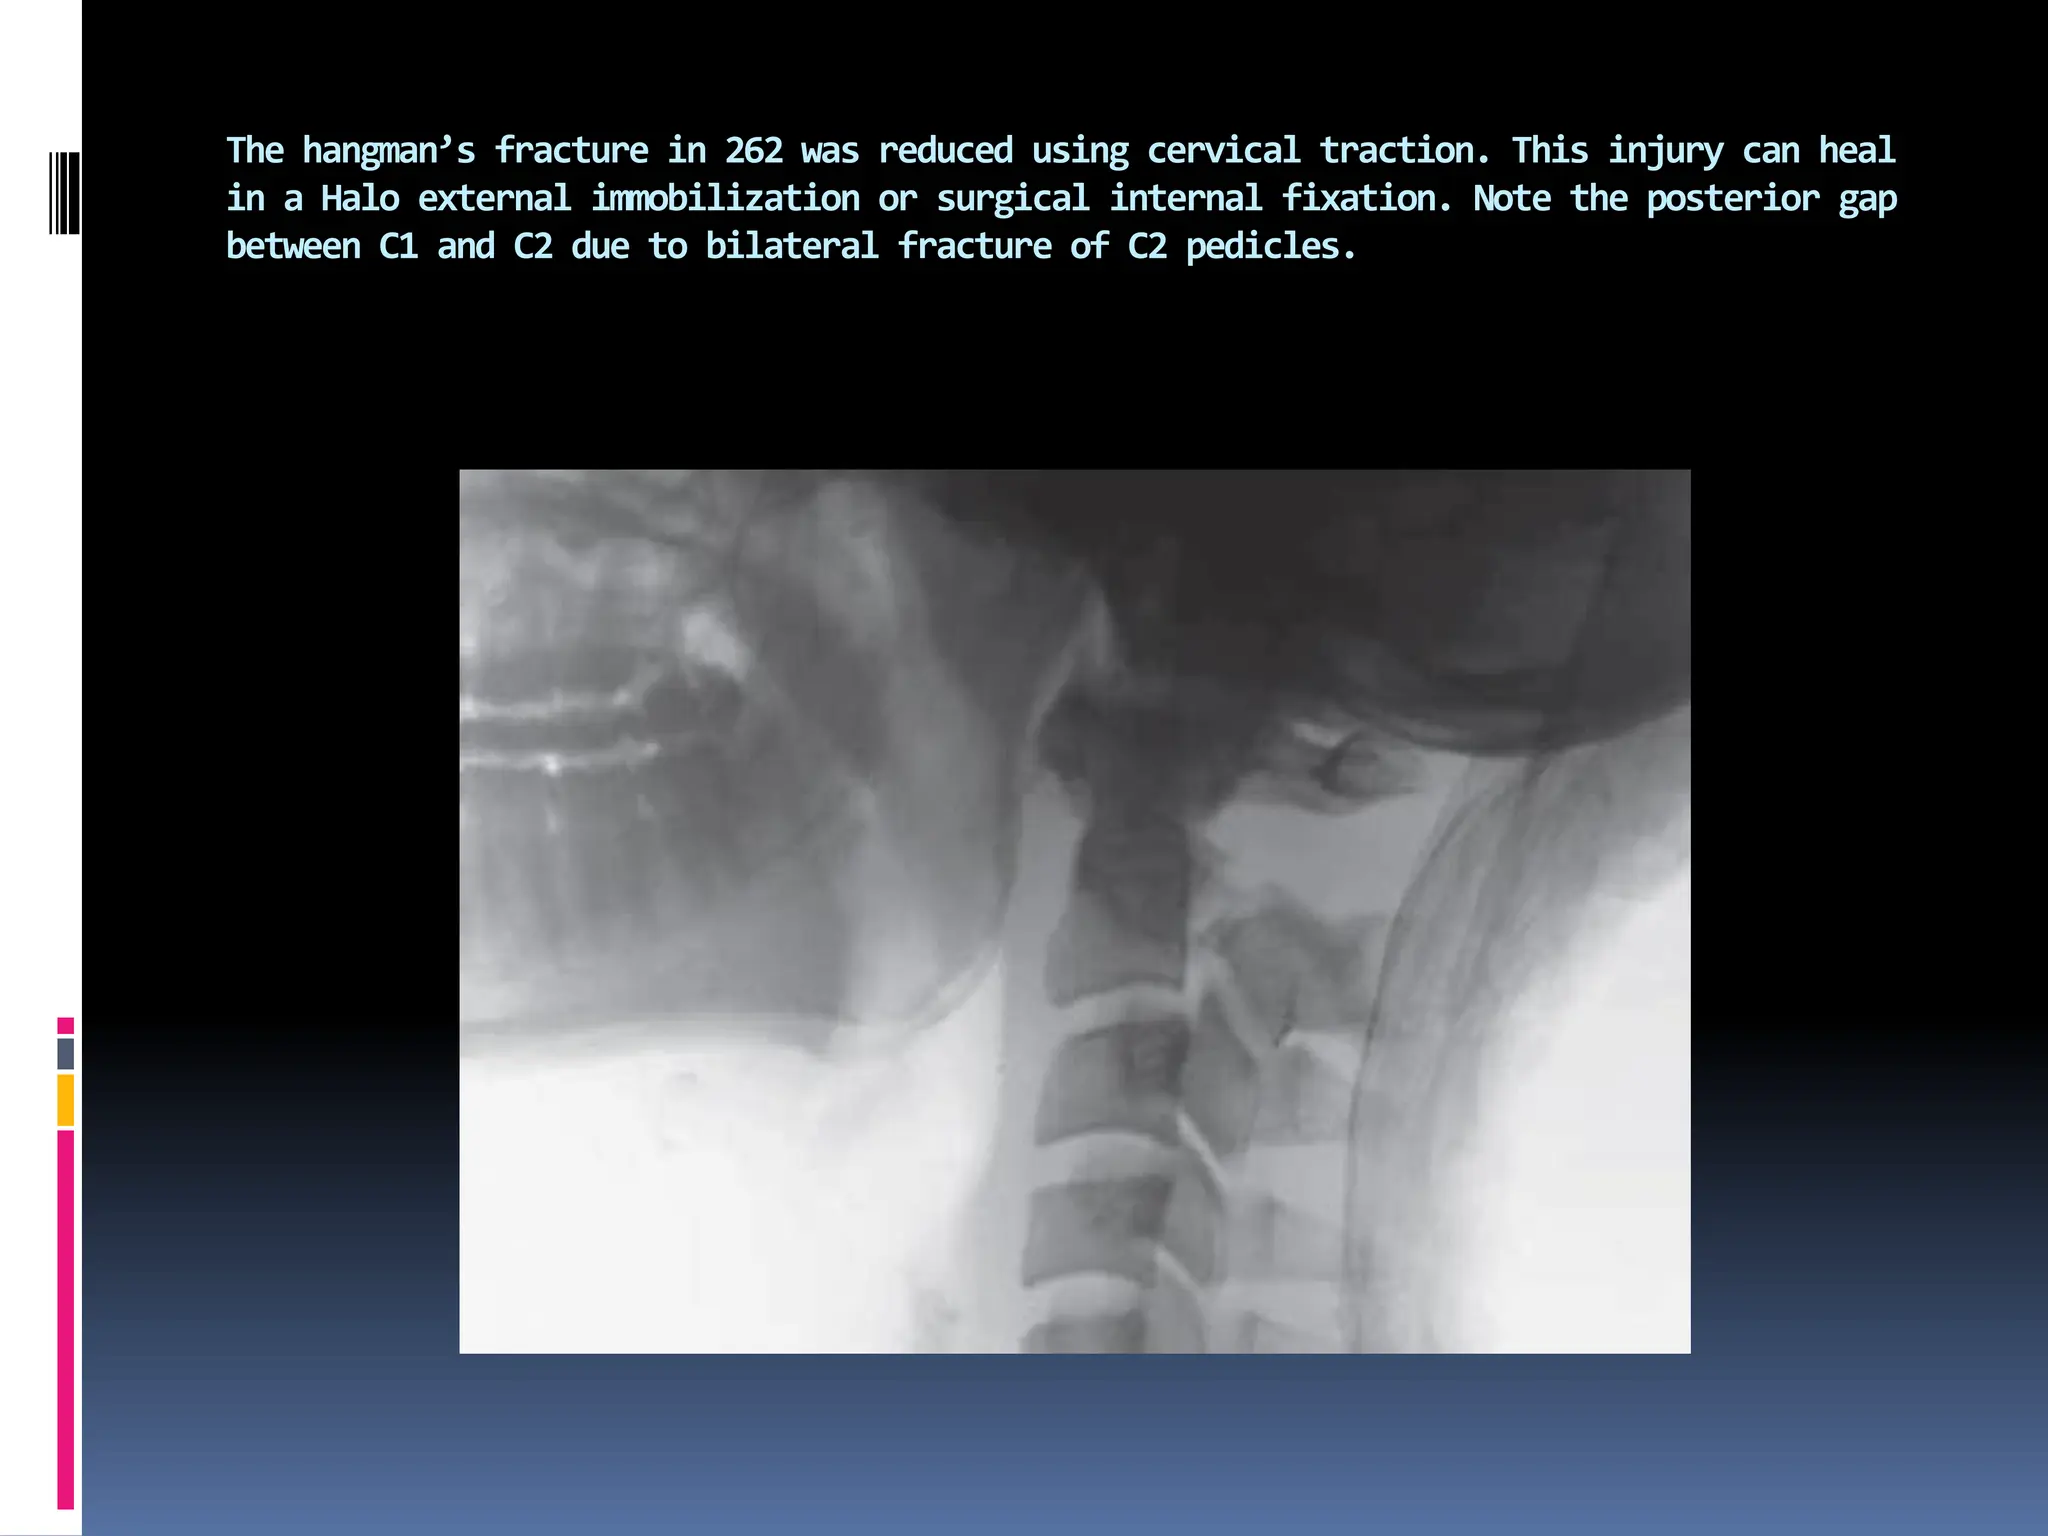

Radiograph showing hangman’s fracture with severe displacement of fracture segments at

C2–3.

The hangman’s fracture in 262 was reduced using cervical traction. This injury can heal

in a Halo external immobilization or surgical internal fixation. Note the posterior gap

between C1 and C2 due to bilateral fracture of C2 pedicles.